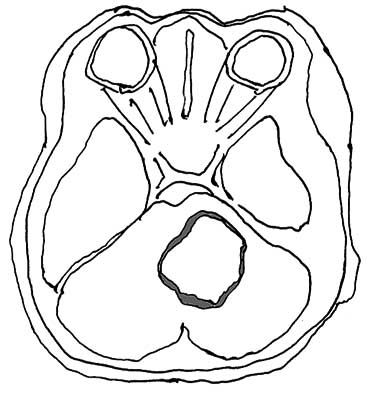

braintumor01.jpg

Case01 43yo female recent headaches, lt. face and hand numbness. 組織はglioblastoma

Initial Dx

Integrated diagnosis; Pending

Histological diagnosis: Glioblastoma

Histological grade: Grade IV

Molecular information: Pending ここには, IHCのmolecularな部分や, mitosisを書き込んでもかまわないがそれ以外の遺伝子mutationなどが強制的にはいってくるのが今の状況.

Case Molecular data(時間とお金をかけて行う)

Molecular surrogate immunohistochemistry:

Molecular assays:

Final, integrated diagnosis

Integrated diagnosis: Glioblastoma, IDH-wild type, WHO gradeIV

Molecular information: IDH wildtype, TP53 mutant, PTEN mutant, MGMT promoter methylation negative, PDGFRA amplified.

われわれがおそらく今までやってきたことは、Histological diagnosisとHistological gradeは自信もってpathologistがやって, Molecular informationについてはできるだけのことをやっていたと. IHCではMIB-indexを出したり, p53を調べたり, IDH1だったら変異タンパクを検出するとか, 99%あるいは98%くらいの診断でよいとおもうんですが, できればこういうシークエンスもやってということなんですね。(高橋Dr)